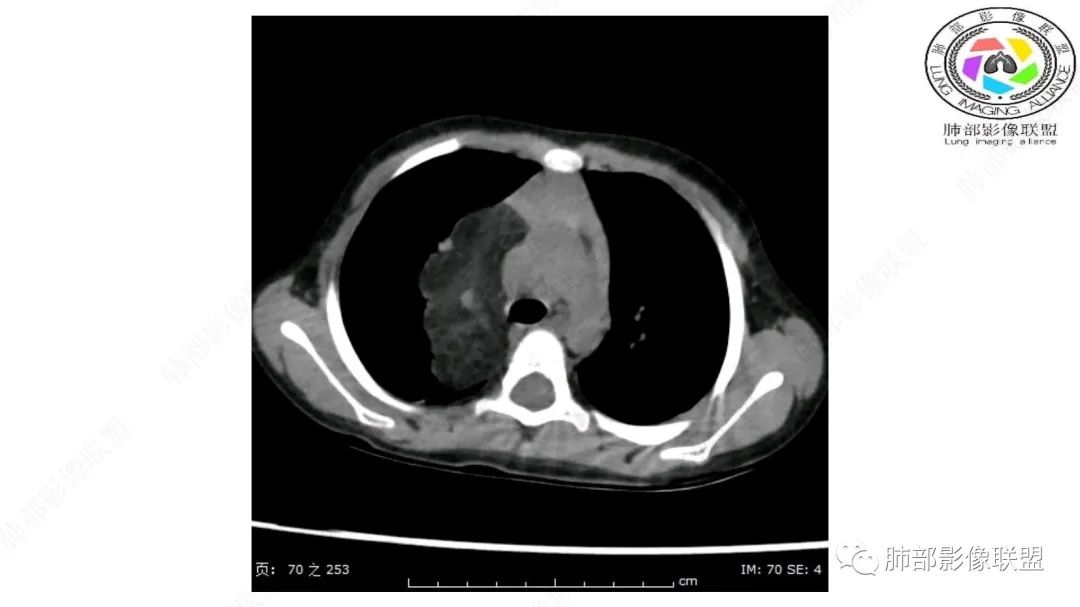

右肺门上方,位于纵隔胸膜旁见巨大肿块,脂肪为主混合密度,内见细小血管影,肿块最大长径与纵隔胸膜平行,包绕右肺上叶肺动脉,右肺上叶及纵隔结构推压,无侵蚀破坏,良性肿瘤,起源纵隔胸膜血管平滑脂脂肪瘤。

跨肺门,包绕肺血管分支,邻近肺组织受压肺不张。

婴幼儿,病变较大,跨肺门,分叶,富含纤维或黏液、含成熟脂肪,破坏力弱或无,浸润性生长模式不明显,未见远处转移。

综合:富含成熟脂肪的、可以有丛状结构的,可以有纤维或黏液的良性或低度恶性肿瘤。常见疾病谱:脂肪瘤、神经纤维瘤样错构瘤、冬眠瘤、血管脂肪瘤、髓脂肪瘤、脂肪母细胞瘤、黏液样脂肪肉瘤。

病灶属于交界区,主体位于肺内,占位效应明显,前方突入胸壁,胸腺受压变形,胸膜显示欠清楚;病灶包绕上叶肺动脉;似乎有体动脉供血。符合肺内的点:包绕上叶肺动脉分支;符合纵隔的点:前方似乎突入胸壁,与胸腺关系比较密切,但是与上腔静脉的关系提示病灶不支持纵隔来源,前纵隔的常规会将上腔静脉受压后移、外移,这是不符合的。

从这个角度符合肺内的,有一点不太踏实的是:似乎突入前胸壁。

内部血管明显,部分病灶密度增高,单纯脂肪瘤不支持。可惜的是:没有提供CT值:是否强化?如果强化,警惕恶性;胸腺肯定不符合,胸腺会将上腔静脉朝后推移。

手术记录:见右肺上叶肿物,肿物与右肺上叶关系密切。与纵隔无粘连,逐步分离肿物,见肿物大小约6cm*5cm,边界清楚,于右肺上叶粘连,边界清楚,肿物包绕右肺上叶血管及支气管。超声刀逐步游离肿物,完整切除肿物,右肺上叶肺组织无破溃,表面无出血。

脂肪母细胞瘤由成熟程度不同的脂肪组织、纤维间隔、黏液基质、小血管丛等间质成分组成,以脂肪组织与黏液样基质为主,其影像学表现取决于上述组织成分。典型的CT和MRI表现为:前后纵隔均可发生,常见于前纵隔;肿块大小不一,直径多在3cm~7cm,密度均匀,CT值呈水样或脂肪密度,脂肪组织密度或信号为主的肿块,其内密度或信号不均匀,可见粗细不一的分隔影,且有结节、片状影,后者可呈轻中度强化;结节状肿瘤包膜完整;弥漫性者包膜不明显,常呈浸润性生长;周围结构为受压和推移改变,可有少量胸腔积液,淋巴结无增大。